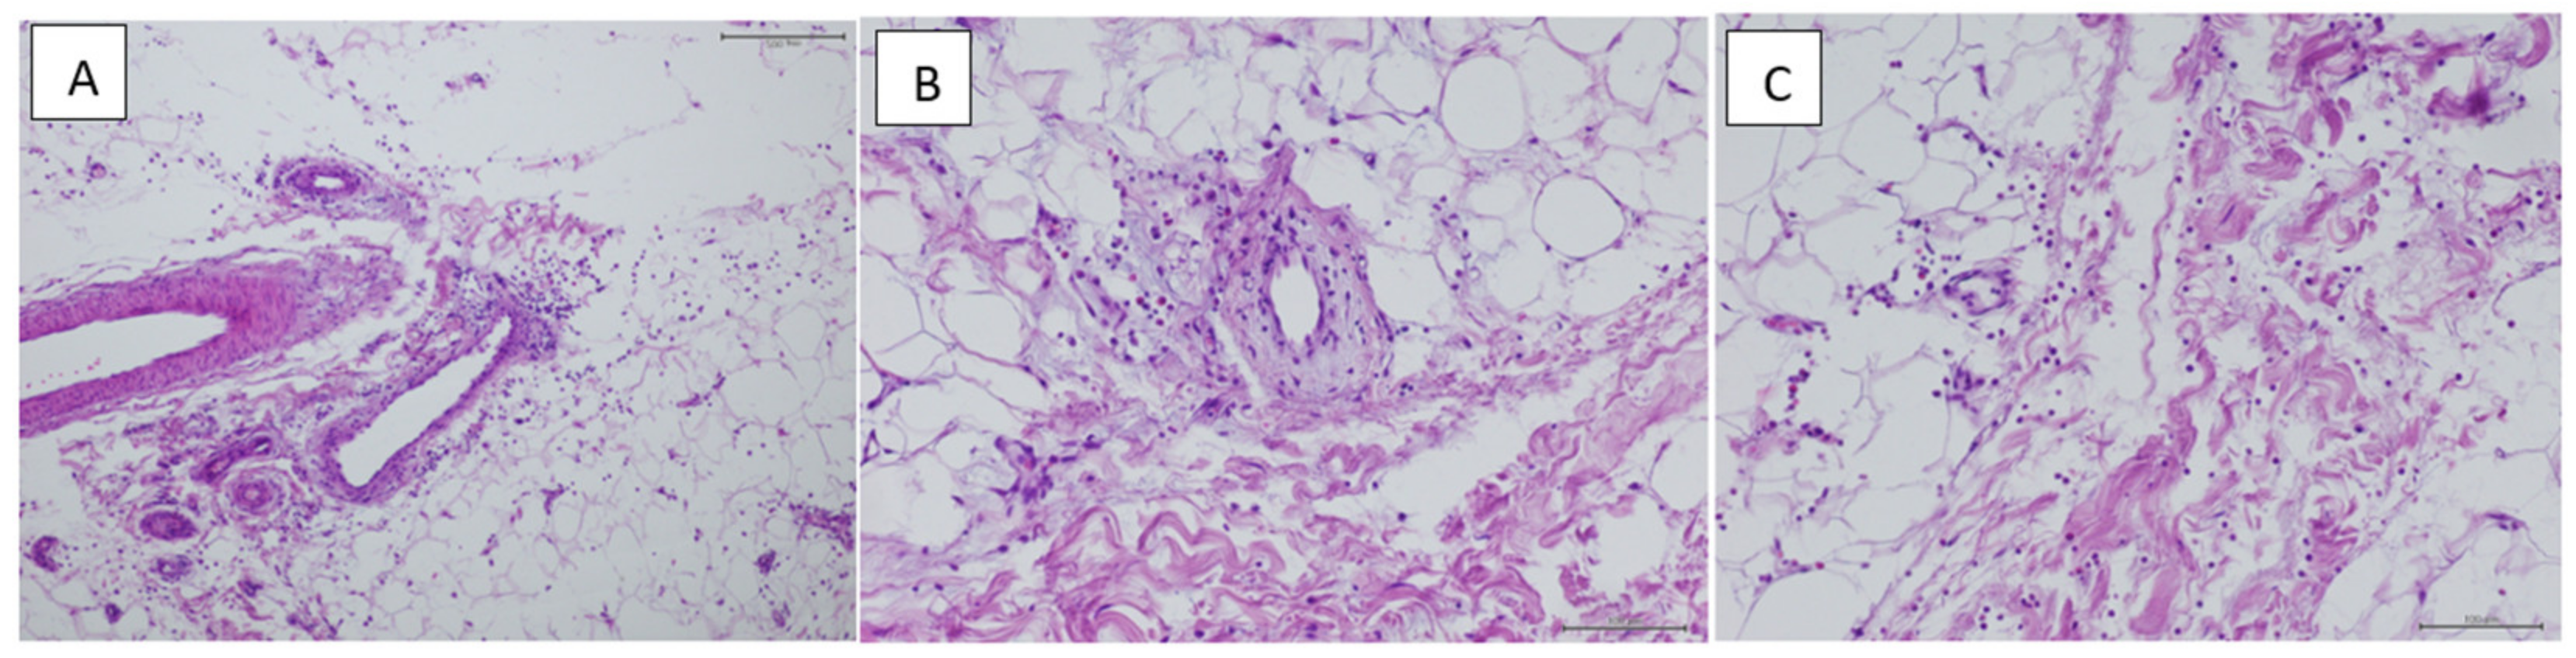

Histology

| Small | (<50 µm) | 10% |

| Medium | (50–69 µm) | 15% |

| Large | (70–89 µm) | 45% |

| Very large | (>90 µm) | 30% |